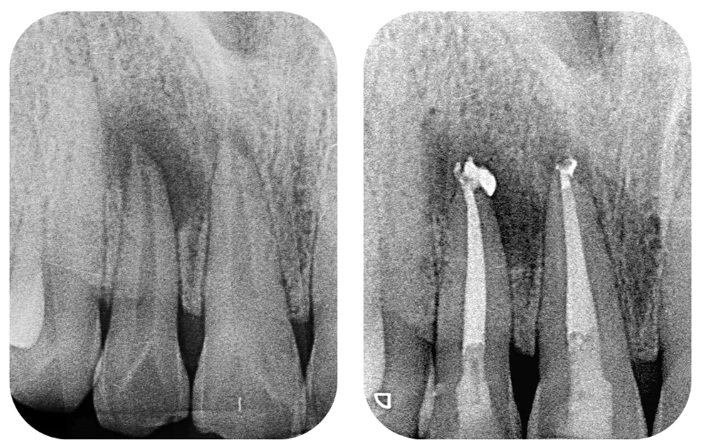

- More Roots and Canals: Front teeth might have one root. A molar can have two, three, or even four roots, each with one or more canals. Finding and cleaning all of them is a precise task.

- Complex Anatomy: The canals inside molar roots can be curved, narrow, or branch out in unexpected ways. It's like cleaning a intricate, microscopic cave system.

- Missed Canals: Remember those complex molar anatomy? Sometimes a tiny, extra canal is missed during cleaning and remains infected.

- Incomplete Cleaning: Severely curved or blocked canals might not be fully cleaned.

Signs of a failing root canal are similar to the original problem: pain, swelling, a recurring pimple on the gum (sinus tract), or sometimes it's only visible on a follow-up X-ray.

If a root canal fails, you have options. An endodontic re-treatment is the first line. This means reopening the tooth, removing the old filling material, finding and cleaning the missed area, and re-filling. It's more complex but can often save the tooth. Another option is an apicoectomy, a minor surgical procedure where the tip of the root is accessed through the gum and bone, the infected tip is removed, and a filling is placed to seal the end. In some cases, if the tooth is not salvageable, extraction becomes necessary.